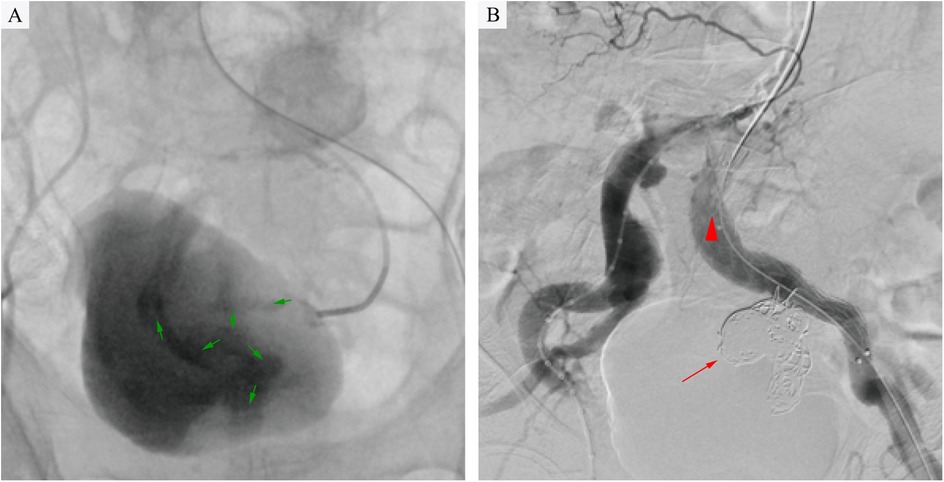

However, on the third day after the endovascular procedure, the patient experienced intermittent lower gastrointestinal bleeding (50–100 ml/day). Colonoscopy was subsequently performed, which revealed complete sloughing of the necrotic tissue at the enteric fistula site, exposing a fistula tract approximately 9 mm in diameter with active oozing (Figures 3A,B). Endoscopic clip hemostasis was then performed (Figure 3C). Following endoscopic hemostasis, the patient was maintained on parenteral nutrition and antibiotics, with close monitoring of hemoglobin levels and fecal occult blood tests. During this period, the patient remained afebrile without chills or fever. Three sets of blood cultures were negative. Hemoglobin levels gradually increased, and the frequency and volume of bloody stools steadily decreased. On post-endoscopic hemostasis day 9, the hemoglobin level was 90 g/L and the fecal occult blood test was negative. On day 11 after endoscopic hemostasis, follow-up endoscopy demonstrated complete closure of the fistula with only mild residual mucosal edema (Figure 3D). Biopsy specimens obtained during the initial emergency endoscopy showed chronic mucosal inflammation, focal necrosis with cholesterol deposition, mixed acute and chronic inflammatory cell infiltration, and multinucleated giant cell reaction. The patient resumed oral intake on day 12 after the initial surgery and was discharged on day 15 without complications. The discharge regimen included enteric-coated aspirin (100 mg/day) and levofloxacin (0.4 g/day). During a 7-month telephone follow-up, the patient reported normal bowel movements without fever or abdominal pain. A follow-up CT scan performed 7 months postoperatively demonstrated complete occlusion of the left internal iliac artery (Figure 4A), patency of the left external iliac artery (Figure 4B), and the stent without foci of gas (Figures 4C–E). The detailed sequence of therapeutic interventions is presented in the treatment timeline (Figure 5). Informed consent was obtained from both the patients and their families.

Figure 3

(A,B) Colonoscopy demonstrated tissue necrosis and fibrinous exudate at the fistula site, with minimal oozing (arrowheads). (C) Hemostasis was achieved via through-the-scope endoscopic clips. (D) On day 11 after endoscopic hemostasis, follow-up endoscopy demonstrated revealed complete fistula closure with mild residual mucosal edema.